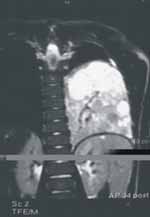

La tomografía computarizada de alta resolución del pulmón mostró imagen heterogénea, localizada en la base izquierda, de 6 por 7 cm, con algunos tabiques, compatible con malformación adenomatoidea quística grado II-III (ver Figura 3).

Figura 3. Tomografía computarizada de alta resolución. Corte transversal y corte coronal

En vista del diagnóstico imagenológico de malformación adenomatoidea quística grado II-III se decidió hacer angiorresonancia, ya que la evolución satisfactoria del niño no correpondía al cuadro clínico de la malformación adenomatoidea.